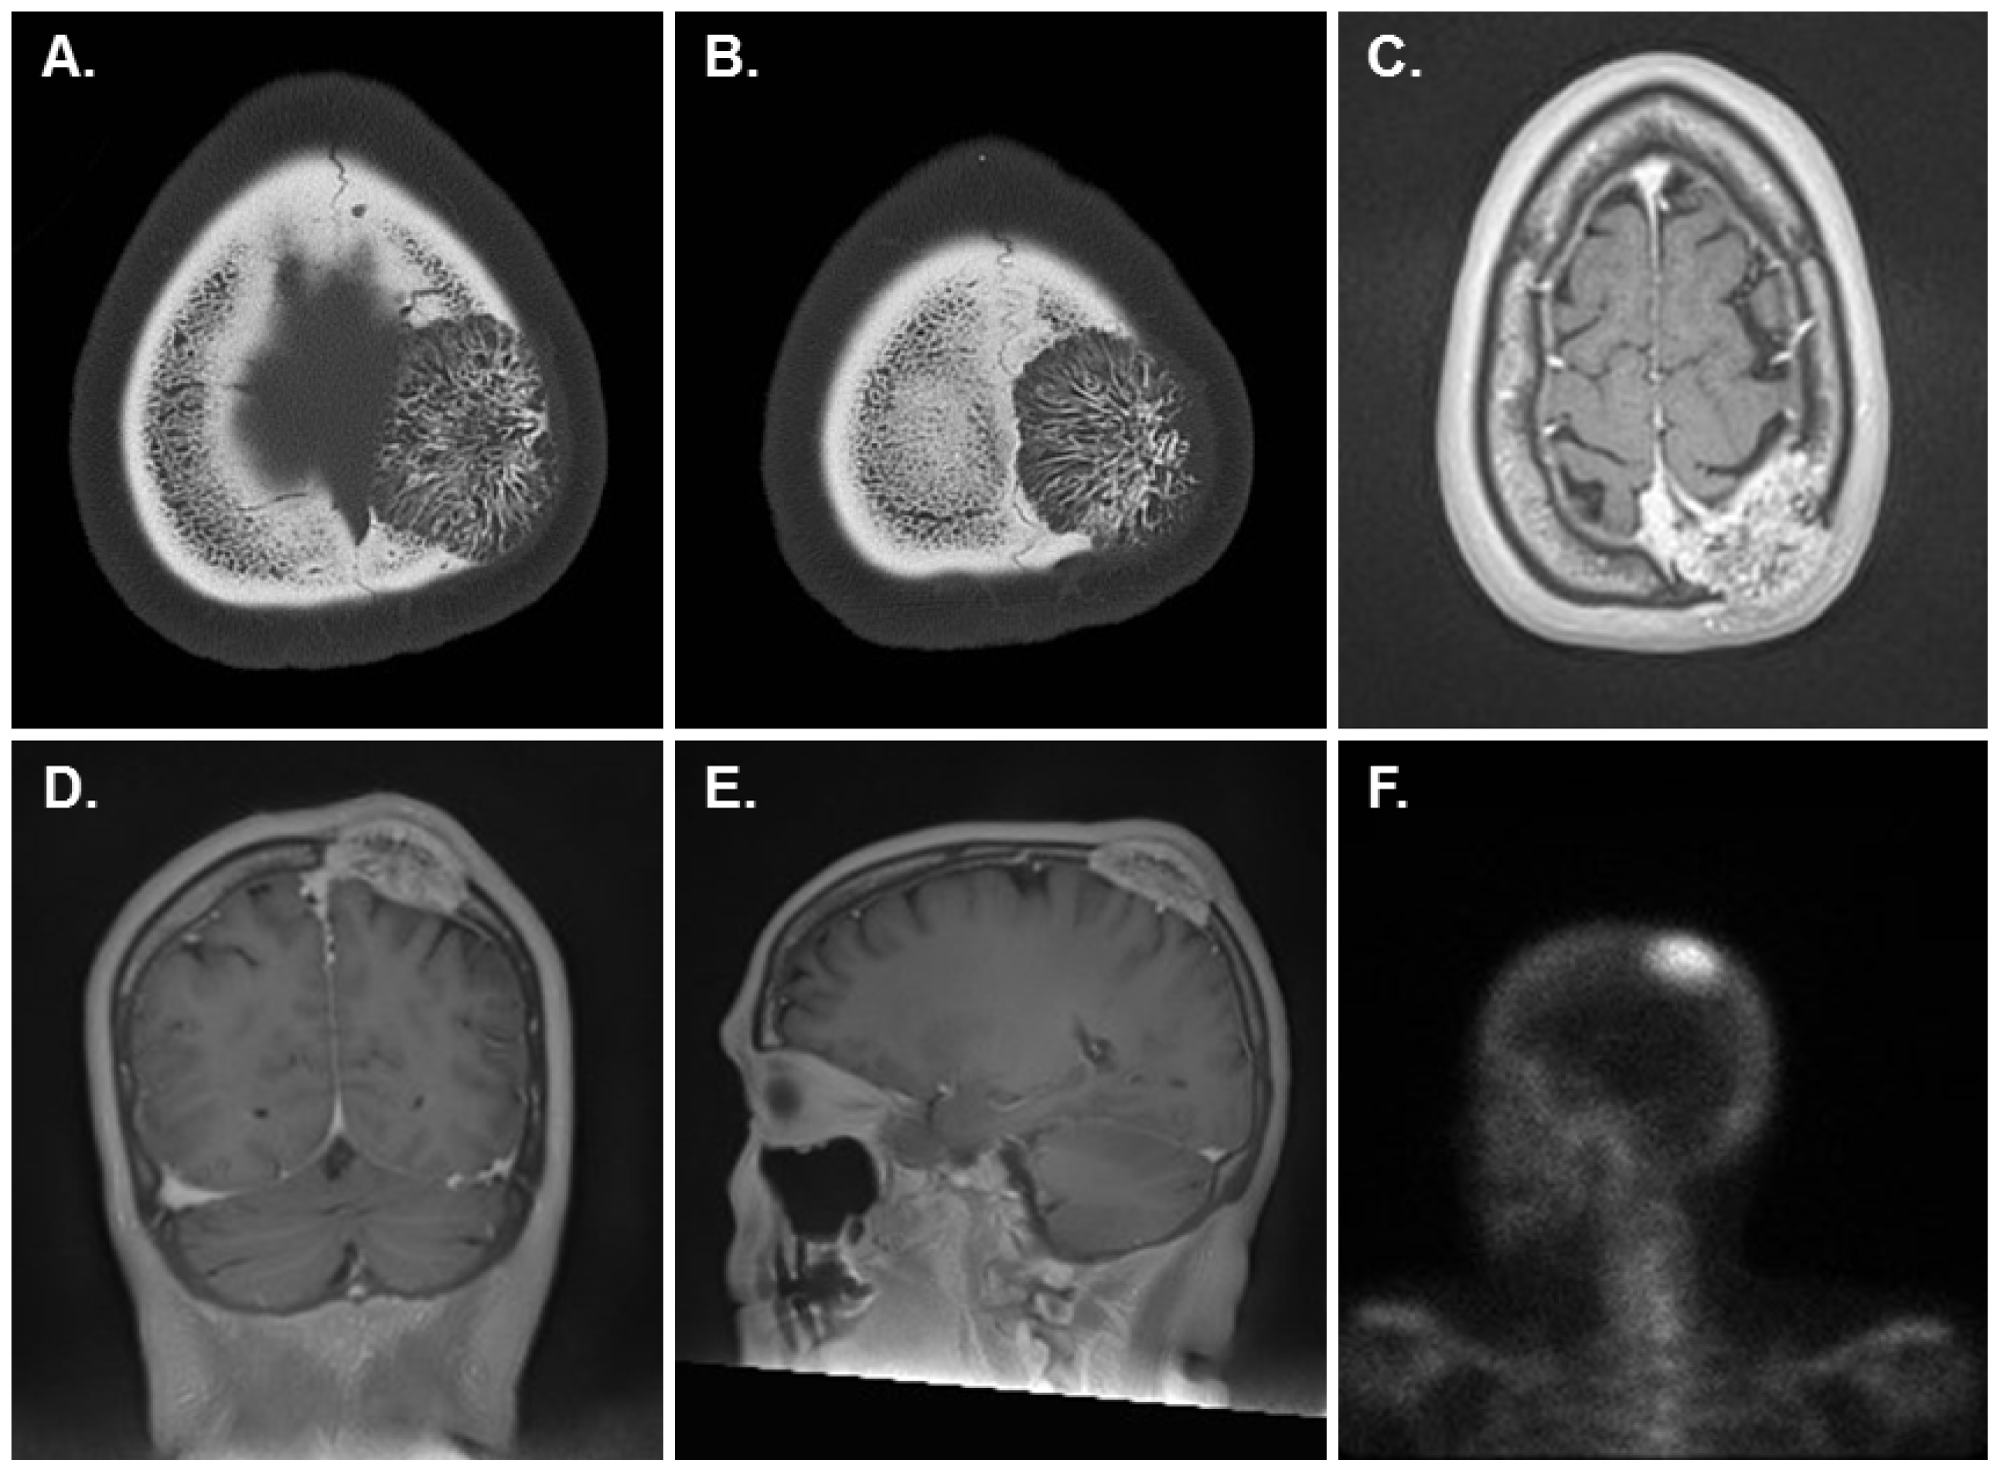

A 61-year-old female with hypertension and arthritis, as well as a history of both squamous cell carcinoma and basal cell carcinoma, was referred to our institute for evaluation of an enlarging palpable left frontoparietal bone lesion. Six months prior to presentation, the patient hit her head on a closet rail and subsequently noted a lump on the left frontoparietal aspect of her scalp. She was then followed up with CT and MRI of the brain with and without contrast, revealing a growing expansile, striated, enhancing lesion in the left frontoparietal cranial bone, which appeared to abut the superior sagittal sinus. The lesion disrupted the inner and outer tables of the cranial bone and indented the extra-axial space of the left frontoparietal region with extension outside of the cortex into the soft tissues. There was no evidence of cerebral parenchymal involvement, except for cerebral compression (Figure 1A, Figure 1B, Figure 1C, Figure 1D and Figure 1E). The differential diagnosis including metastatic disease or an atypical hemangioma was radiologically considered. Subsequently, a total body bone scan was also performed and only revealed this solitary lesion in the skull (Figure 1F). Given the rapid growth and etiological uncertainty of the bone lesion, a left frontoparietal craniectomy for complete resection of the mass with subsequent cranioplasty was performed. The excised lesional skull bone was sent for histopathological examination. Clinical follow-up with the patient showed no recurrence of this tumor.

Figure 1: Radiographic images of the left frontoparietal mass. A,B) CT head without contrast revealed an expansile, spiculated osseous lesion in the left frontoparietal calvarium with a small soft tissue component along its superficial surface (A, B, Axial); C,D,E) T1-weighted MRI brain with and without contrast identified an expansile, striated, enhancing left frontoparietal bone lesion which indented the extra-axial space of the left parietal region with extension outside the cortex into the soft tissues (C, Axial; D, Coronal; E, Sagittal); F) Total body bone scan revealed a solitary lesion in the skull (left lateral view of the head is shown). View Figure 1